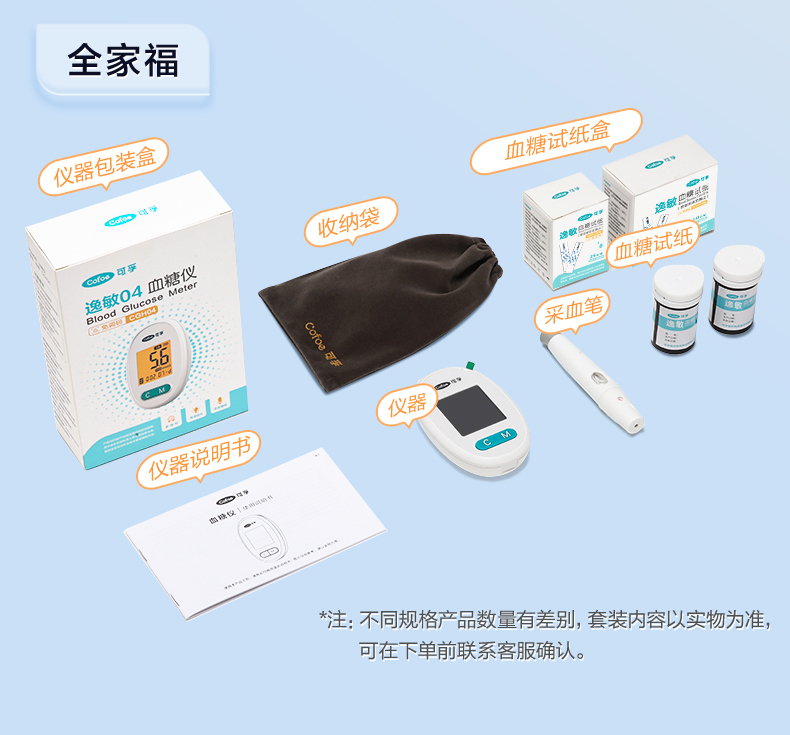

可孚新国标血糖测试仪家用测糖仪试纸官方旗舰店测血糖的仪器孕妇

Фото та опис товару